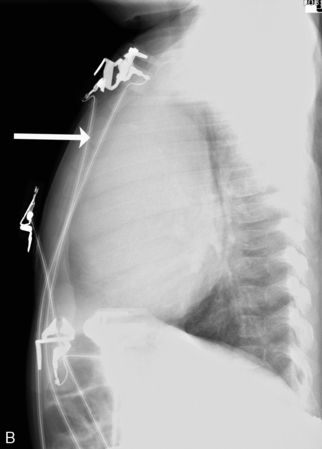

A pneumothorax will produce an air-tissue interface in the pleural cavity because the pneumothorax contains only air with no pulmonary vascular markings, whereas the lung contains air, tissues, and vessels. The presence of a significant pneumothorax will cause partial or complete collapse of the adjacent (ipsilateral) lung. Note that free pleural air will accumulate in the highest portions of the chest so that the location of the air is influenced by the patient’s position when the X-ray is obtained. In an upright film, free pleural air is typically observed above the apex of the lung, whereas in a supine film the air may accumulate along the anterior and lateral aspects of the lung and along the diaphragm (Fig. 10-7).

image

Fig. 10-7 Tension pneumothorax. This film was obtained as part of a routine daily chest radiograph to monitor for endotracheal tube placement in this 18-year-old male with methicillin-resistant Staphylococcus aureus necrotizing fascitis. This is a supine AP film that demonstrates near total atelectasis of the right lung. The pneumothorax is visible along the inferior and lateral aspects of the right chest, with a shift of the cardiac silhouette to the left. There is clear visualization of the lung-air interface (arrows) seen along the lateral and inferior margins of the right lung. This is a tension pneumothorax because the mediastinum is markedly shifted and the right hemidiaphragm is flattened out of the field of view.